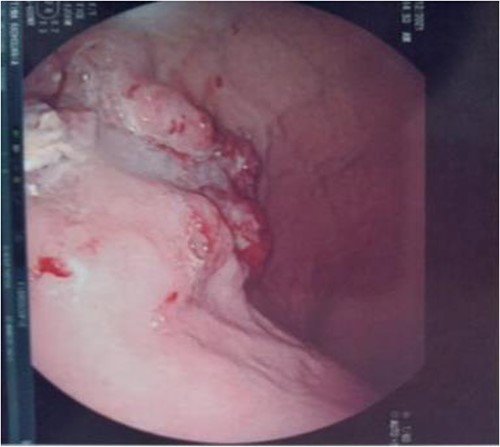

Serum carcinoembryonic antigen was 4.3 μg/L (normal value <5.1 μg/L). Biological tests showed normal platelet count and prothrombin time was 70%. Hemoglobin level was 12.2 g/dL. His biochemical tests showed hypoalbuminemia (31 g/dl). The patient was scheduled for a colonoscopy. However, a large bowel obstruction occurred during the bowel preparation. Thus, computed tomography (CT) scan of the abdomen and the pelvis was performed revealing circumferential wall thickening narrowing the rectal lumen and invading the prostate and the mesorectum with upstream bowel dilatation without extrinsic mass, lymphadenopathy, or metastasis. The patient underwent colostomy without incident. Colonoscopy was performed after colostomy, showing large, circumferential, infiltrative, friable, and stenosing submucosal mass with erythematous overlying rectal epithelium, taking on the appearance of grape clusters (shown in Fig. 1). Mucosal biopsies showed invasive poorly differentiated carcinoma referring at first a neuroendocrine tumor. Second mucosal biopsies were performed showing inflammatory modifications of the rectal mucosa without any malignancy. Third mucosal biopsies concluded to poorly differentiated carcinoma. Magnetic resonance imaging (MRI) of the pelvis showed circumferential wall thickening narrowing the rectal lumen and invading posterior peripheral area of the prostate, the bladder, the left seminal vesicle, and the mesorectum (shown in Fig. 2). The radiologist suggest a rectal cancer (RC) invading the urogenital tract or a PC invading the rectum subject to non-injected MRI. In fact, the MRI was interrupted before gadolinium injection because the patient was claustrophobic. Serum prostate specific antigen (PSA) was then ordered and it was raised at 25.59 μg/L (normal value<4 μg/L). Therefore, macro-biopsies of the rectal mucosa using snare loop were performed showing a poorly differentiated infiltrative carcinoma and immunohistochemical (IHC) stains were strongly positive for PSA and pancytokeratin and negative for anti-CD56 (shown in Fig. 3). Then, a clear diagnosis of PC invading the rectum was established. Bone scintigraphy was performed and was normal. The patient was referred to urology department. He underwent surgical castration. Then, androgen depletion therapy (ADT) was started. A total of 3 months later, there was a good response with his PSA level dropping to 0.5 μg/L. About 3 years after, patient is still alive, but PSA level has increased to 52 μg/L. The CT scan of the thorax, the abdomen, and the pelvis showed a prostatic hypertrophy with loss of the security edging with the rectum without any metastatic involvement.

Large, circumferential, infiltrative, friable submucosal mass with erythematous overlying rectal epithelium, taking on the appearance of grape clusters.

In our case, the patient experienced digestive symptoms without any lower urinary tract symptoms. Colonoscopy findings were uncommon showing a circumferential, infiltrative, friable, and stenosing submucosal mass, taking on the appearance of grape clusters. In historically reported cases, the diagnosis of PC was confirmed by histology obtained by endoscopic ultrasound with transrectal needle biopsy of the prostate or surgical biopsies [6]. In our case, PC invading the rectum was suspected after CT scan and MRI. Serum PSA was not requested in the beginning but seeing the radiological findings; it was ordered and was high suggesting a PC. Histology was not contributive initially at three times, what prompted us to perform macro-biopsies of rectal mucosa showing a poorly differentiated infiltrative carcinoma. The IHC stains were strongly positive for PSA.